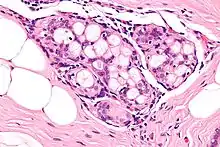

Micrograph of collagenous spherulosis with the characteristic histomorphology - intratubular eosinophilic material with a spoke-like arrangement. H&E stain.

Collagenous spherulosis is characterized by a tubular/cribriform architecture with intratubular eosinophilic material that classically is arranged like the spokes of a wheel ("radial spikes"). There is usually no mitotic activity, and two cells populations (epithelial & myoepithelial) are present, like in benign breast glands.

The lesions are typically small (less than 50 spherules per lesion, less than 100 micrometers in size) and may be multifocal.